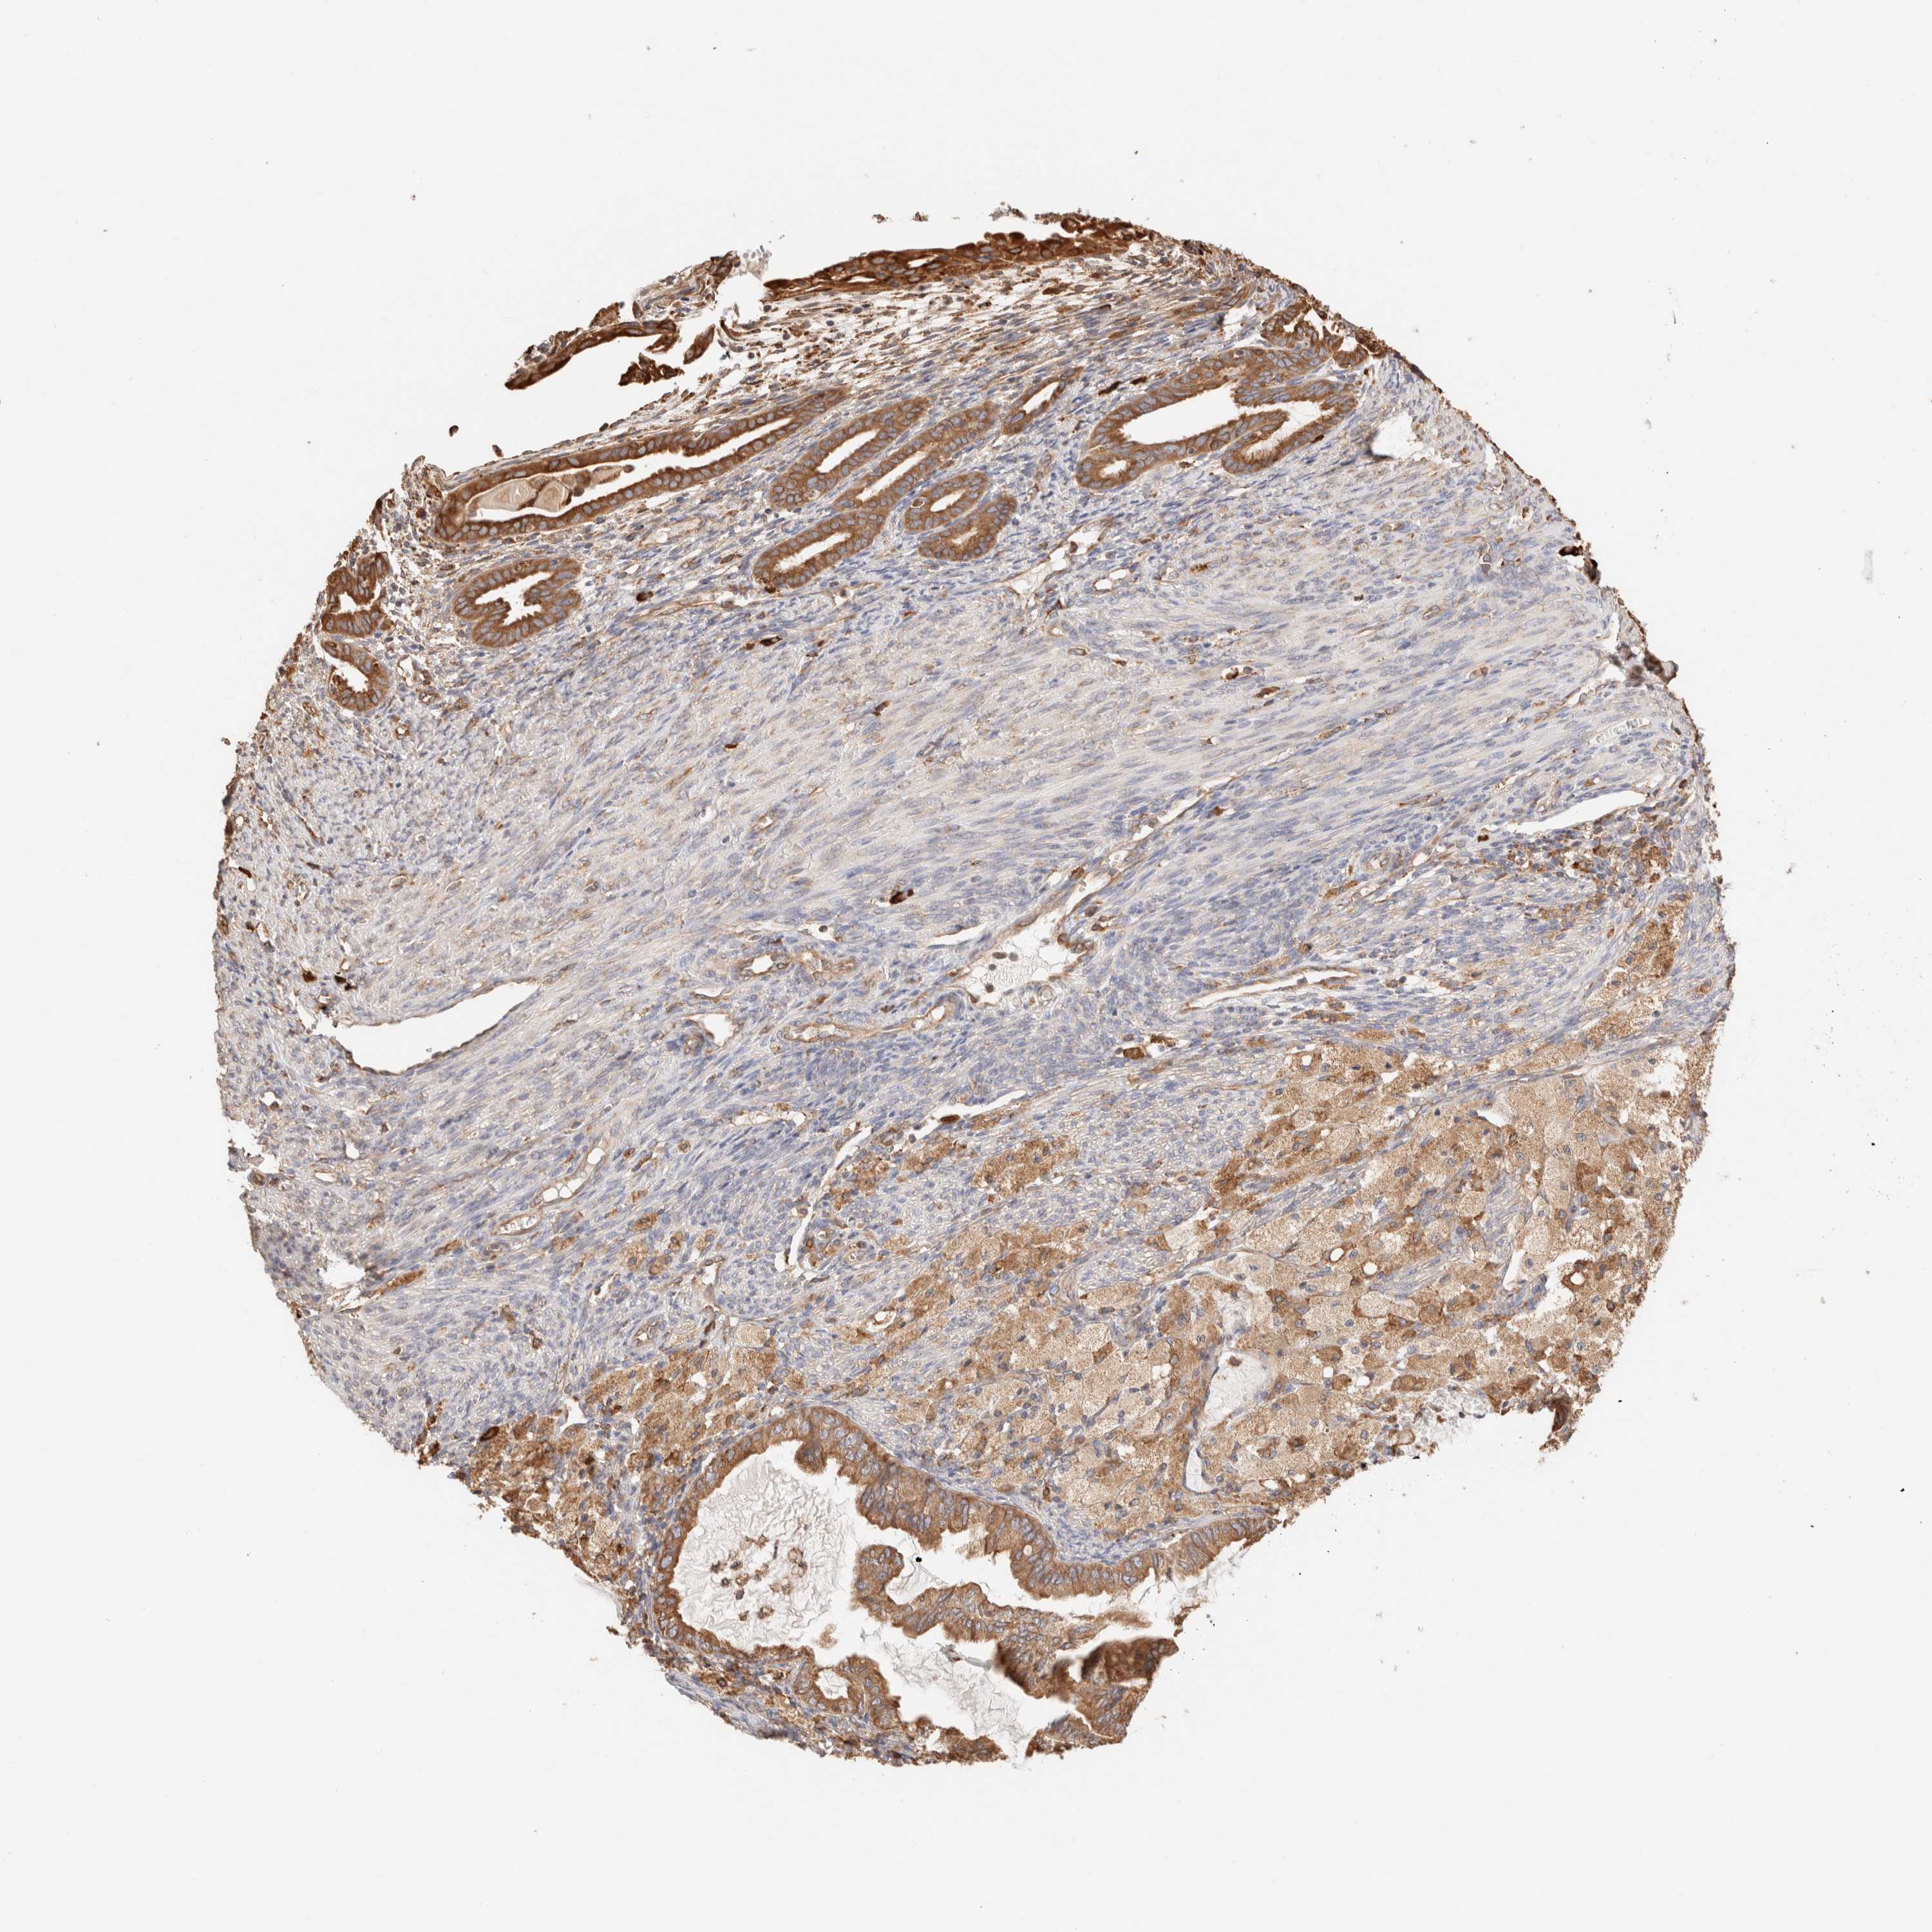

CERVICAL CANCER - Protein expressioni

A mouse-over function shows sample information and annotation data. Click on an image to view it in a full screen mode. Samples can be filtered based on level of antibody staining by selecting one or several of the following categories: high, medium, low and not detected. The assay and annotation is described here.

Note that samples used for immunohistochemistry by the Human Protein Atlas do not correspond to samples in the TCGA dataset.

Antibody stainingi

Antibody staining in the annotated cell types in the current human tissue is reported as not detected, low, medium, or high, based on conventional immunohistochemistry profiling in selected tissues. This score is based on the combination of the staining intensity and fraction of stained cells.

Each image is clickable and will lead to virtual microscopy that enables deeper exploration of all samples and also displays staining intensity scores, fraction scores and subcellular localization as well as patient and tissue information for each sample.

Antibody HPA007641

Antibody CAB022464

Staining

High

Medium

Low

Not detected

Intensity

Strong

Moderate

Weak

Negative

Quantity

>75%

75%-25%

<25%

None

Location

Nuclear

Cytoplasmic/membranous

Cytoplasmic/membranous,nuclear

Squamous cell carcinoma, NOS

Adenocarcinoma, NOS